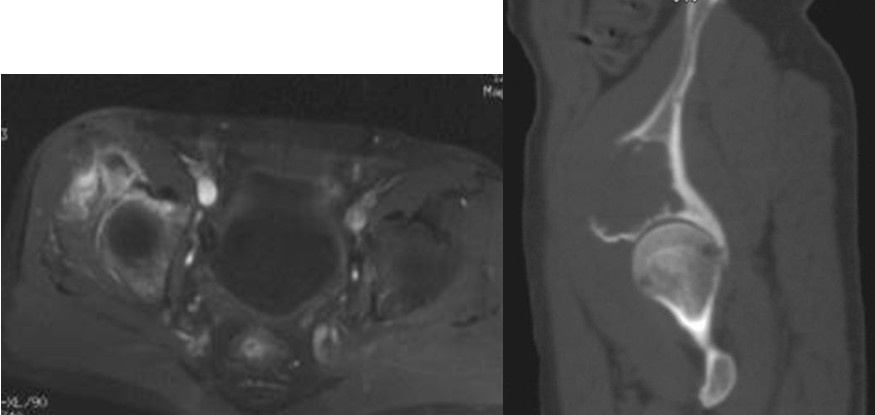

图3,女,55岁,肺癌髋臼转移, Harrington II型

Ⅱ型:髋臼内侧壁缺损,而周边骨质完好。采用普通髋臼会导致假体及骨水泥早期向内侧移位。对于这种情况,应采用特殊设计的带翼髋臼网杯将应力引至髋臼缘。安装时在保持髋臼假体正确解剖位置的同时需注意将网杯的翼放置在完整的髋臼缘,因为部分髋臼边缘可能存在破坏。可以采用后外侧入路,通常无需大转子截骨,尽量使用长颈人工头,以防止粗隆部撞击网杯延伸缘。股骨粗隆部,股骨干有潜在骨折时,应使用长柄髓内针的人工股骨头。术后第一天病人即可下地负重活动。